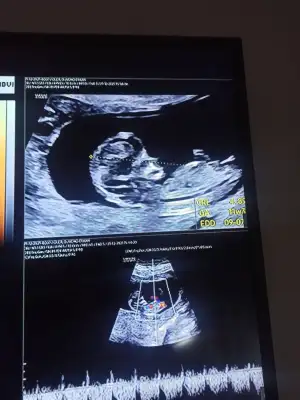

10+6 nub teorisine gore cinsiyeti nedir 🤗

• IMG_20211222_120246.webp

IMG_20211222_120246.webp

32 KB · Görüntüleme: 69